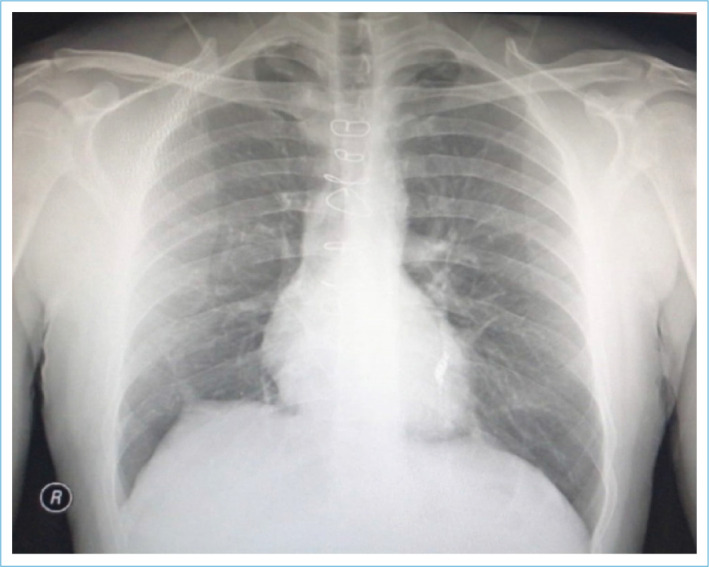

Behçet's Syndrome (BS) is a chronic vasculitis of unknown etiology. Arterial involvement occurring in the pulmonary artery is associated with poor prognosis. It may cause pulmonary thrombus (PTE) and aneurysm (PAA) which may also lead to a rare complication, intracardiac thrombus. PAA and PTE can be complications of BS and are associated with high morbidity and mortality. A 30-year-old male patient had a fever of 38.4°C, recurrent oral-genital ulcers, shortness of breath, cough, and sputum. In this case report, medical history, clinical and laboratory examinations, radiography, echocardiography, and computer tomography imaging examinations were performed. PAA, PTE, intracardiac and left popliteal vein thrombosis, and infective endocarditis were present. The patient was diagnosed with BS according to the International Study Group criteria. Surgery was performed for intracardiac thrombus. Vegetation within the thrombus was demonstrated histopathologically. The patient's clinical condition and laboratory tests improved with intervention and medical treatments. The patient with BS, PAA, PTE, intracardiac thrombus, and infective endocarditis was successfully treated with pulmonary embolization, antibiotics, and systemic immunosuppression, despite its rarity, poor prognosis, and high morbidity and mortality rates.

Abstract Image